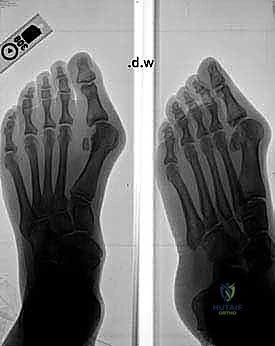

FIG 2 • A–D. Preoperative and postoperative radiographs.